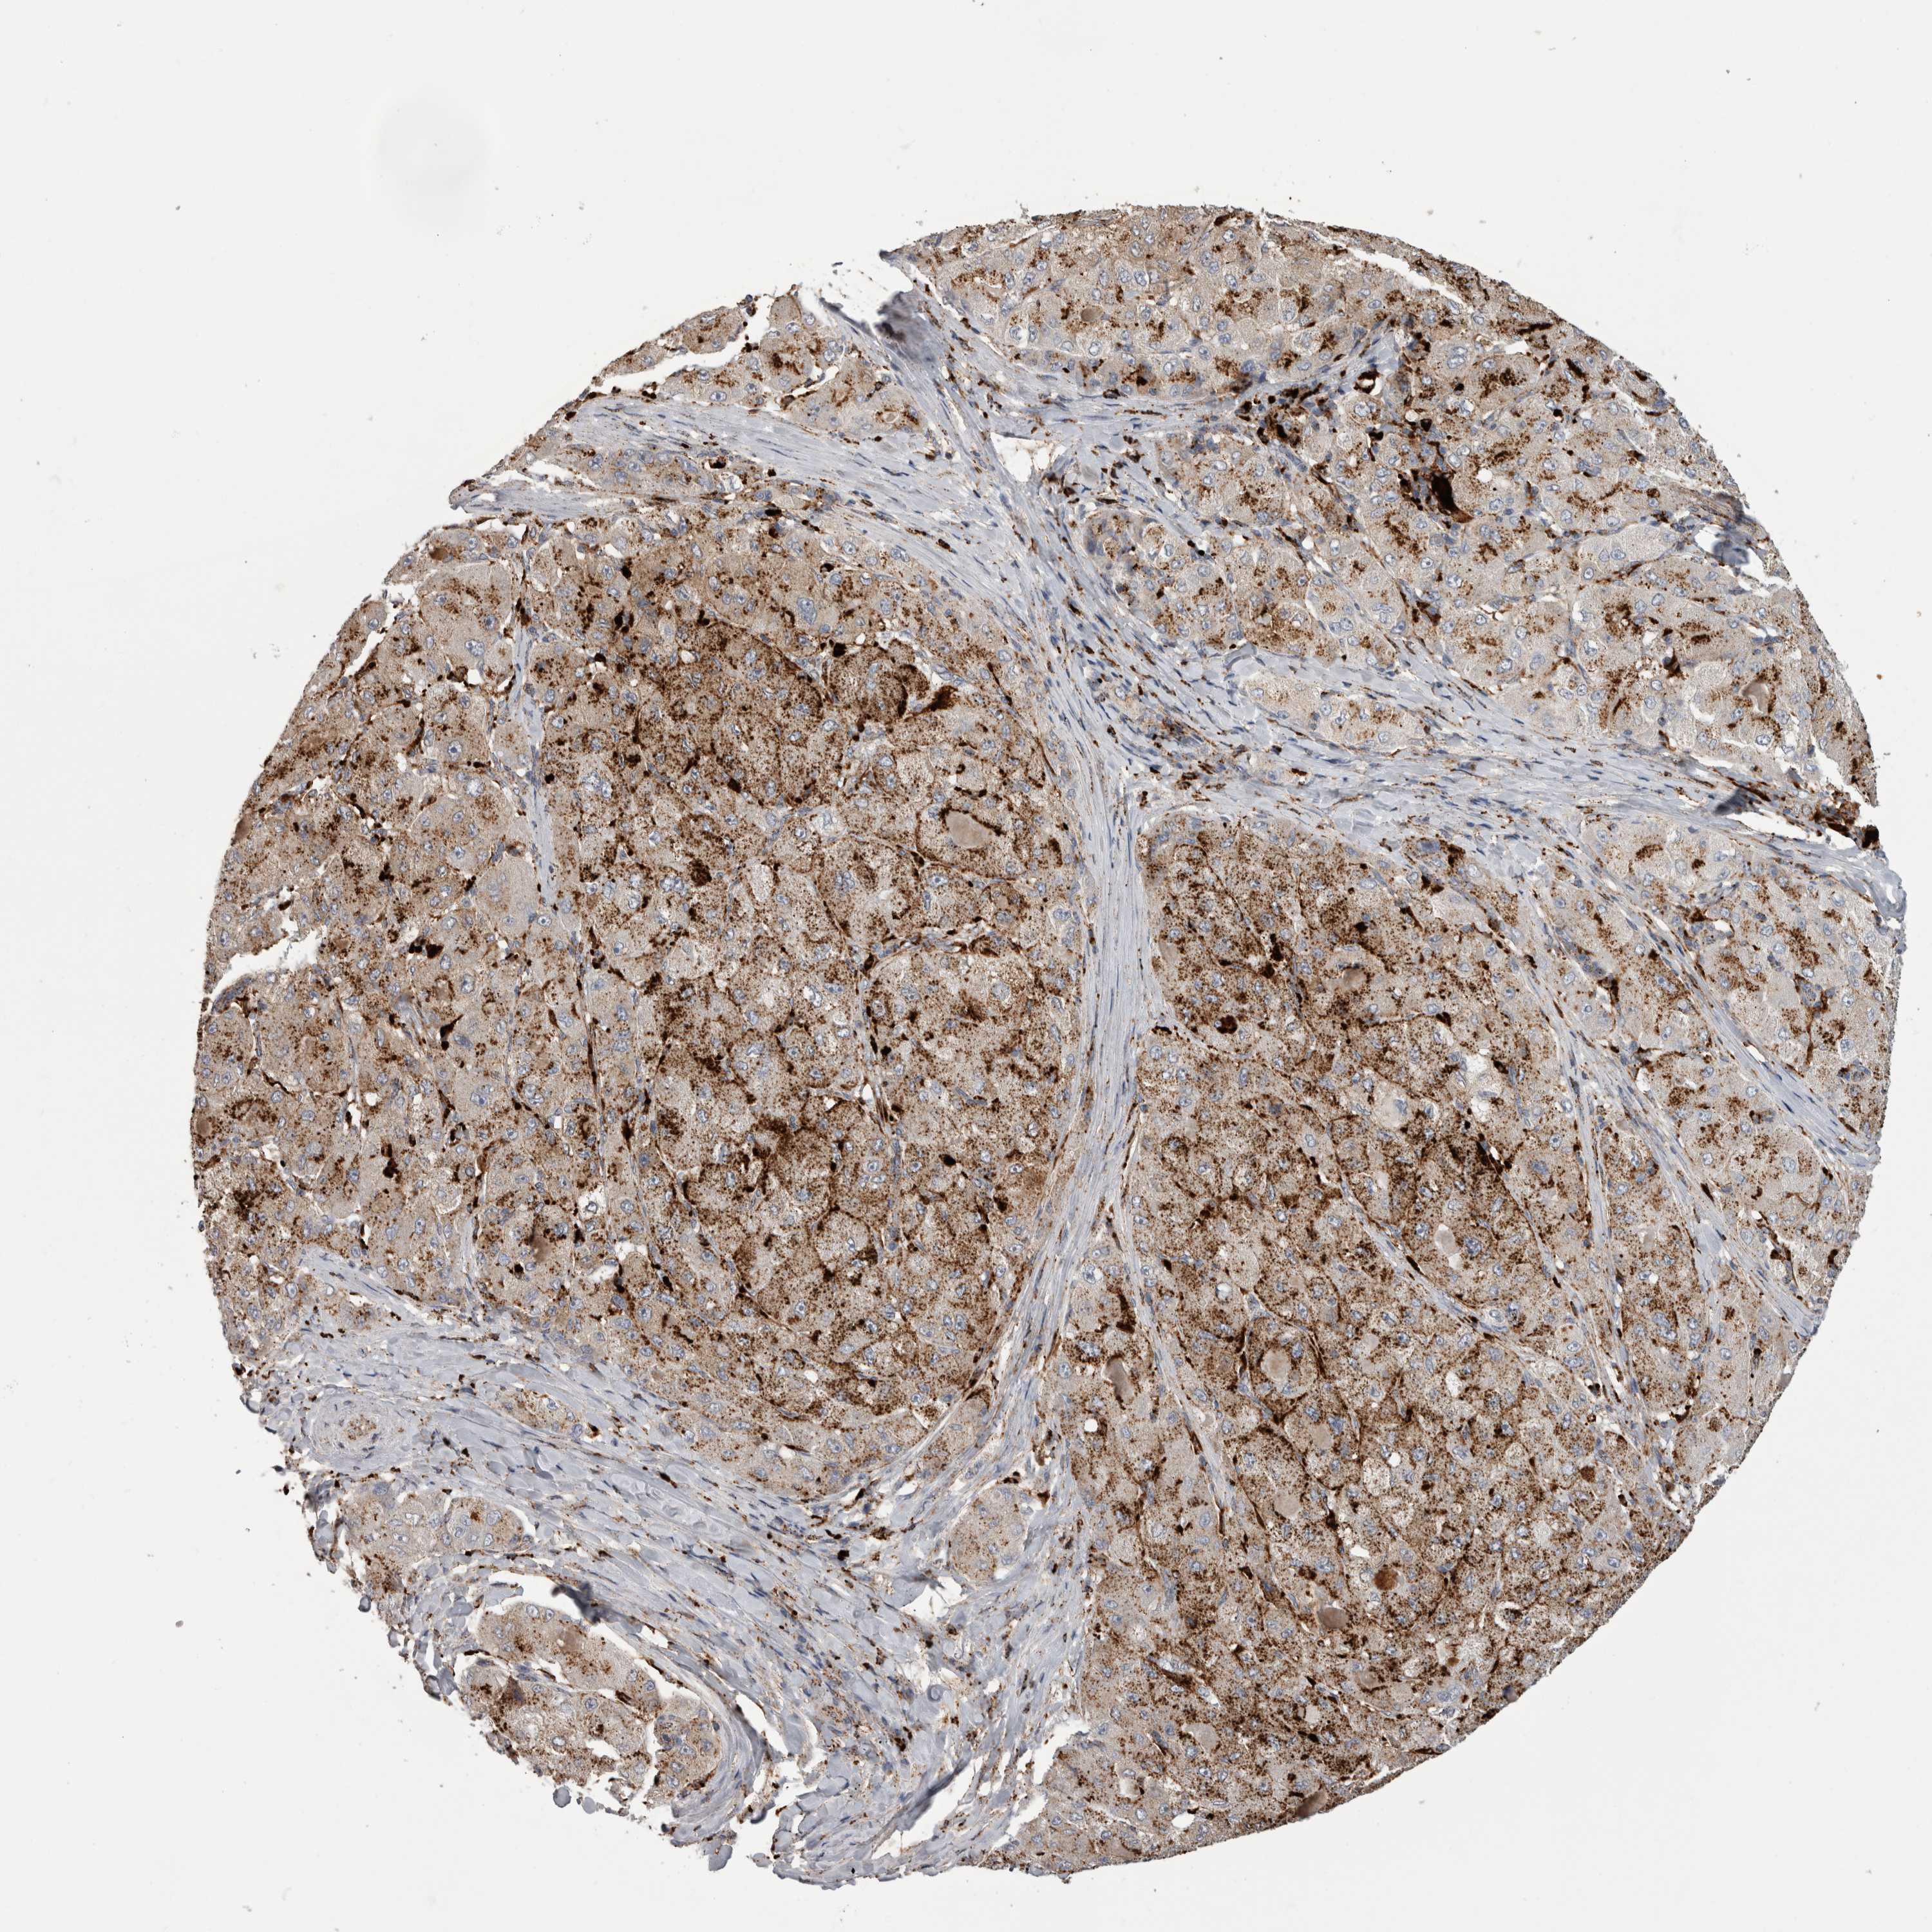

LIVER CANCER - Protein expressioni

A mouse-over function shows sample information and annotation data. Click on an image to view it in a full screen mode. Samples can be filtered based on level of antibody staining by selecting one or several of the following categories: high, medium, low and not detected. The assay and annotation is described here.

Note that samples used for immunohistochemistry by the Human Protein Atlas do not correspond to samples in the TCGA dataset.

Antibody stainingi

Antibody staining in the annotated cell types in the current human tissue is reported as not detected, low, medium, or high, based on conventional immunohistochemistry profiling in selected tissues. This score is based on the combination of the staining intensity and fraction of stained cells.

Each image is clickable and will lead to virtual microscopy that enables deeper exploration of all samples and also displays staining intensity scores, fraction scores and subcellular localization as well as patient and tissue information for each sample.

Antibody HPA049876

Antibody HPA053504

Antibody CAB025114

Staining

High

Medium

Low

Not detected

Intensity

Strong

Moderate

Weak

Negative

Quantity

>75%

75%-25%

<25%

None

Location

Nuclear

Cytoplasmic/membranous

Cytoplasmic/membranous,nuclear

Carcinoma, Hepatocellular, NOS

Cholangiocarcinoma